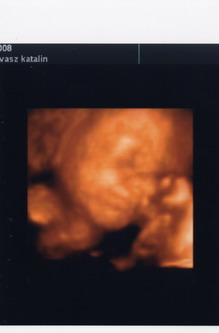

Nagyon jó volt a 4D :lol: Egyértelműen kisfiam van, meg is mutatta, még 4D-ben is! :lol: Apja büszke volt ám!

A váróban még vígan rugdosott, de ahogy felfeküdtem az ágyra bealudt! :roll: Végig aludta az egészet! Ettől féltem!

De még az volt a szerencse hogy nem takarta el az arcát! Olyan helyes kis pofija van! :D Bár a farfekvése miatt az arca volt a legtávolabb az ultrahang fejtől, így kissé homályos volt néha. :(

De felraktam őket a www-re! :lol: Van amit én csináltam itthon fényképpel a videóról, mert csak 2 db-ot adott a doki.

A doki (Dr. Lollok Zoltán) nagyon rendes volt, vagy 15xpróbált jobb képeket csinálni, de messze volt a kis feje. Lelkiismeretes volt, meg vagyok elégedve! Mindent elmagyarázott, megmutatott. 19 perces a video.

Minden rendben van amúgy, pont 26hét és 4-5 napra tehetők az adatok! :lol:

930gramm :lol: A feje is szép kerek7,1cm :lol:

Kicsit több a magzatvízem, de doki azt mondta hogy ez még elmegy! Remélem nem lesz belőle gond! :roll:

Megmutogatta a szerveit, még egyszer nyelt is magzatvizet, látszott ahogy lefolyik a torkán :shock: tök jó volt! :lol: